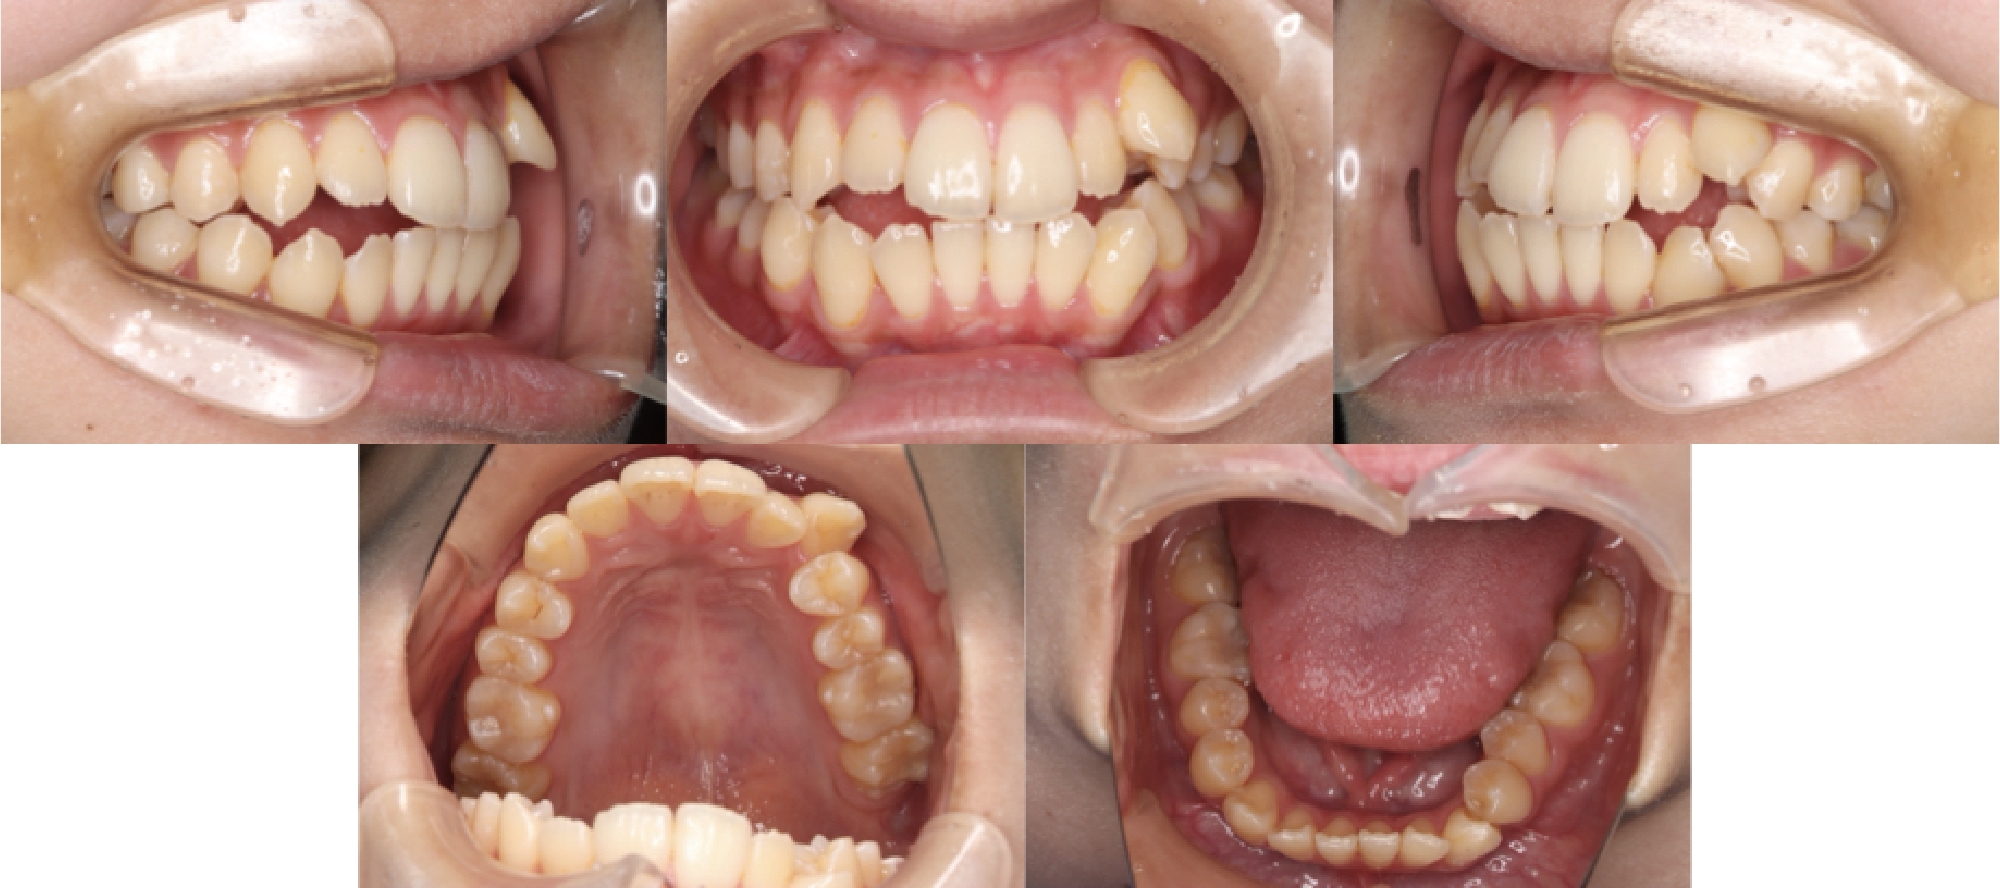

3DCTの治療例

初診時口腔内写真

治療終了時

治療が終わる頃の歯の位置は、事前に作成した3Dセットアップで想定した「骨の中で無理のない位置」とほぼ一致しています。※症例により個人差があります。